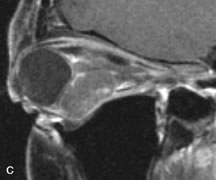

Pleomorphic adenomas demonstrate long T1 and T2 signal characteristics. They may show heterogeneity on T2-weighted images74 and moderate to marked enhancement with contrast.75 Signal characteristics of adenoid cystic carcinoma include hypointensity to fat on T1-weighted images, hyperintensity to fat with increased T2 weighting, and isointensity to fat on proton density-weighted studies (Fig. 23).31,75 Secondary bony alterations of the lacrimal fossa associated with lacrimal gland tumors, such as remodeling (benign mixed tumor) or destruction (adenoid cystic carcinoma), are seen indirectly on MR images; however, bone windows on CT scans provide better delineation of these changes. In contrast to the round or globular appearance of benign or malignant epithelial tumors of the lacrimal gland, lymphoproliferative tumors usually appear to be molding or draping onto the globe and the surrounding bony orbit.

Fig. 23. A. T2-weighted and (B and C) postcontrast fat-suppressed T1-weighted MR scans demonstrate an infiltrative lacrimal region mass than invades the lateral rectus muscle (arrows). This highly cellular lesion is seen to have a very hypointense appearance on the T2-weighted scan.